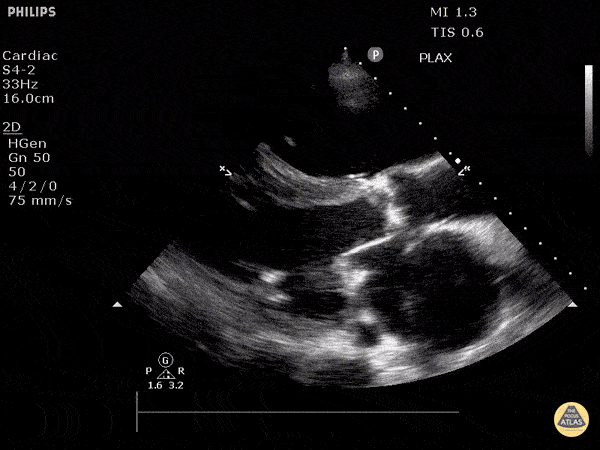

https://www.thepocusatlas.com/valvulopathy

View: Unspecified Parasternal Long Axis Parasternal Short Axis Apical Four-Chamber Subcostal Four-Chamber Subcostal Inferior Vena Cava Right Upper Quadrant Left Upper Quadrant Suprapubic Longitudinal Suprapubic Transverse Subxiphoid Anterior Thoracic Phrenic